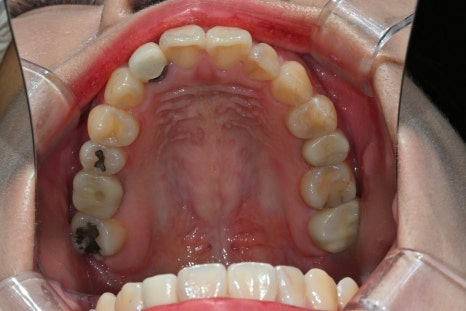

This patient was a 27-year-old woman who visited us because of aesthetic issues with an upper front tooth crown treated about 10 years ago.

A black line visible at the gums

A color difference from the surrounding teeth

An unnatural look in the front teeth

As time passes, upper front tooth crowns can look different from the original result as the gums recede or the internal structure changes. In such cases, rather than simple maintenance, it is necessary to improve them naturally through retreatment.